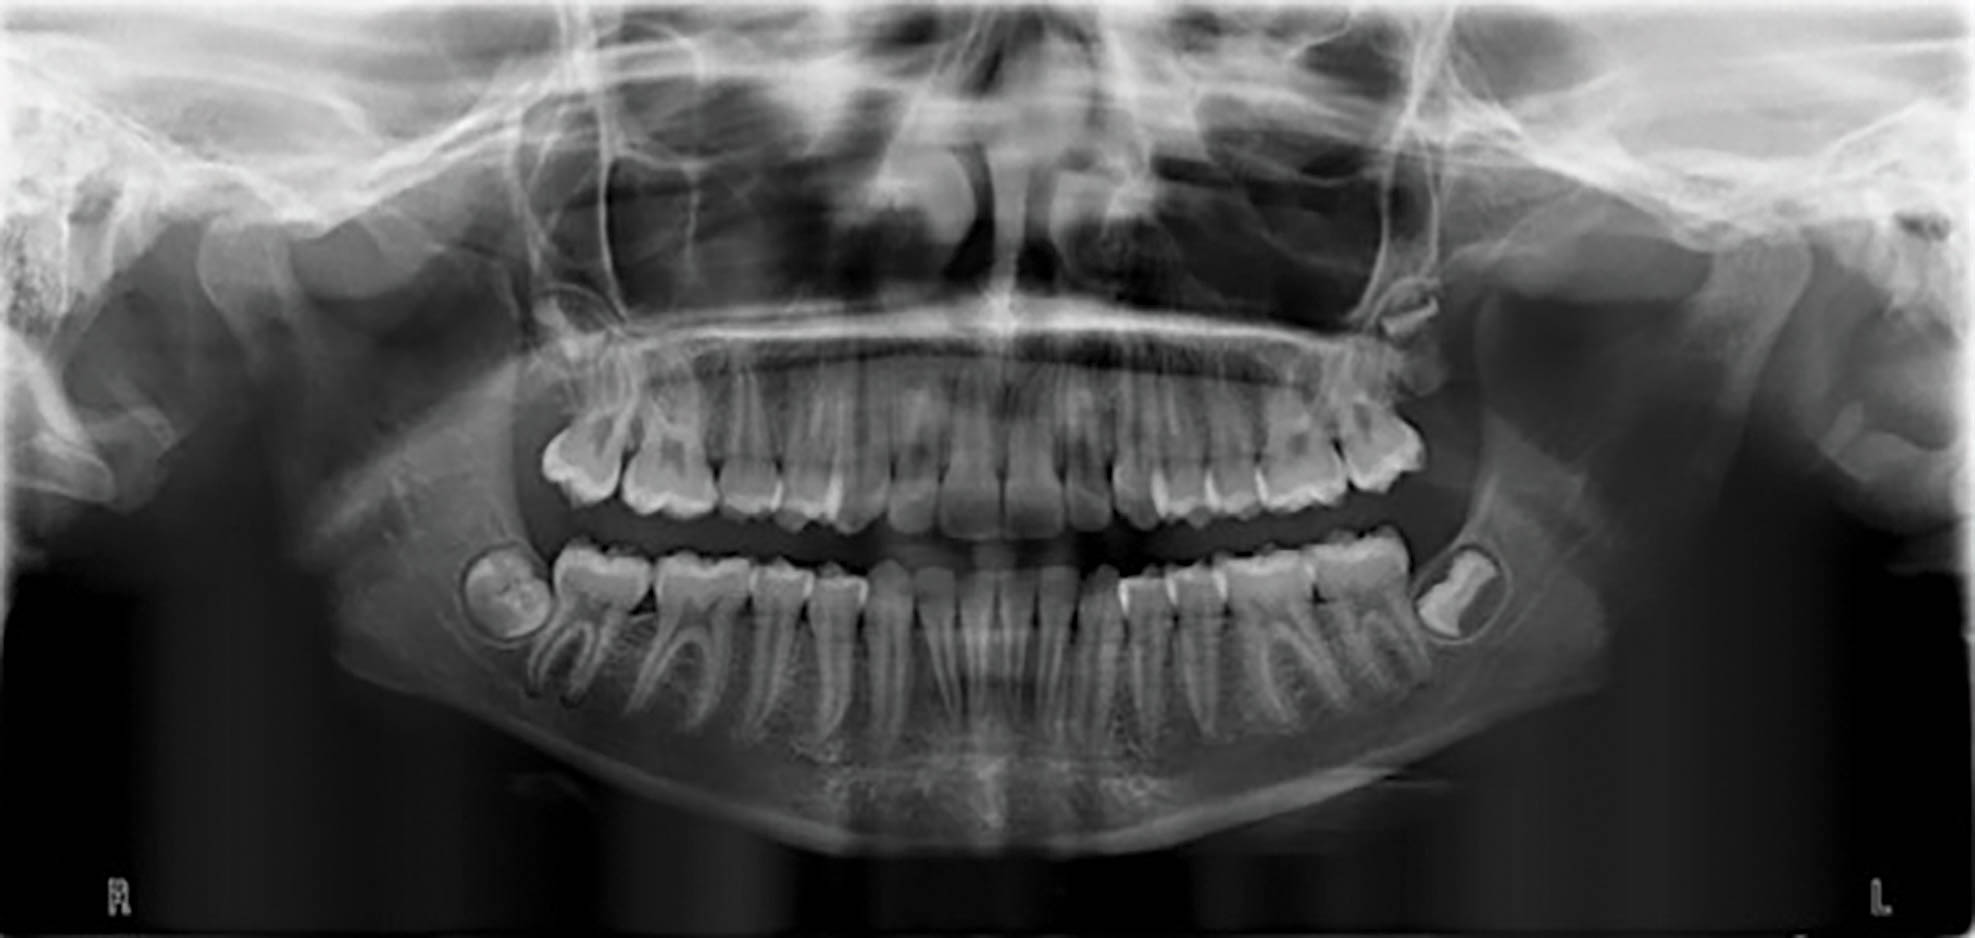

بیمار یک دختر ۱۴ ساله با اکلوژن است. دیپ بایت متوسط تا شدید و کرادینگ متوسط هر دو فک دارد و کانین راست بالا او در کراس است (شکل 68-6 الی 70-6). در این بیمار میخواهیم نحوه اصلاح دیپ بایت و کراس کانین راست بالا را بررسی کنیم.

شکل 68-6

شکل 69-6

شکل 70-6